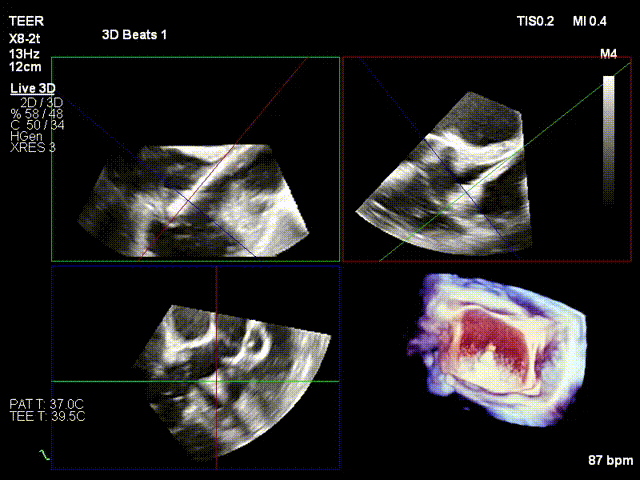

Surgical Procedure

After the patient was placed under general anesthesia, the jugular vein was punctured intraoperatively to establish surgical access. An 18Fr delivery sheath was advanced along a stiff guidewire to the mid-inferior right atrium, and the delivery system was introduced under ultrasound guidance. A 12T K-Clip® device was implanted at the posteroseptal commissure and another 12T K-Clip® device at the anteroposterior commissure respectively. The angle between the device and the annulus plane was adjusted through catheter deflection and rotation to direct the tip of the clip device to the target position. Under ultrasound MPR mode, the anchoring screw was deployed into the annulus. After confirming stable traction, the clamping arms were opened and apposed to the annulus, followed by retraction of the anchoring component to close the clamping arms for annuloplasty. The surgical effect was evaluated as satisfactory, and the clip components were then released.

Deployment of the anchoring component under the MPR view

Opening the clamping arms, adjusting the orientation and apposing to the annulus

Closing the clip

Efficacy evaluation after implantation of the first clip

Implanting the second clip at the anteroposterior commissure following the same procedure